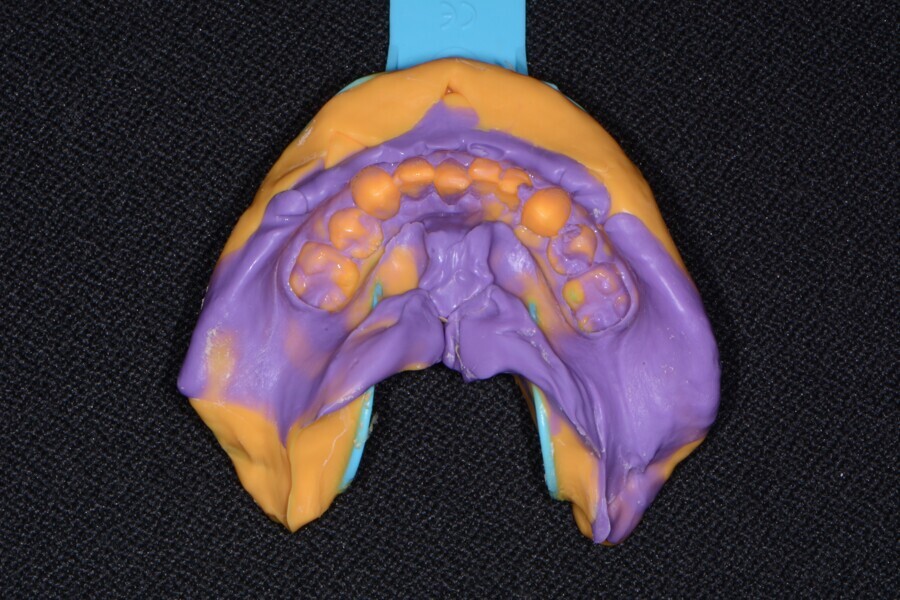

Fig. 8: Mandibular impression (Kettenbach).